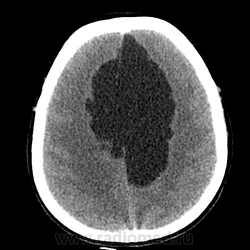

Мало что понимаю в КТ, но как то на ОНМК не тянет. Не могу понять почему сигнал (извините привыкла все сигналами оценивать) от образования какой же что и от желудочка?!

На объем как то тоже не похоже. , сигнал равномерный и такой же как и от ликвора. Если расценивать как последствия ОНМК так это как должно было " рвануть" да еще и с поражением желудочков - не пациент бы вряд ли выжел. Как же сложно в этом к/т ! Не знаю может это глупо, но у меня пока впечатление о врожденной патологии мозга. А с контрастом не делали ? Или вам и так все понятно, Сергей Николаевич , тогда поделитесь мыслями пожалуйста.

Создается впечатление о нехватке/недостатке мозгового вещества.

Действительно любопытно! Только сканов мало. Пока мысль о кисте полости межжелудочковой перегородки. Нет ли там где препятствия или изолированная киста?))

Эпидермоидная киста?

Я бы может сказала что здесь агенезия мозолистого тела. Как мне не хватает МРТ данных (. Агенезия ? Перегородки. Сергей Николаевич подскажите возраст пожалуйста. Здесь должна быть выраженная неврологическая клиника. Расскажите побольше о пациенте.

Эпидермоид может расти, при ТИА может быть случайной находкой. А тут ещё окклюзионная гидроцефалия.

Может, это две межполушарные арахноидальные кисты?

Больному около 55 лет, клинику дает не сколько само образование, а компрессия структур мозга, базально вообще беда (отчасти видно компреммию некоторых базальных цистерн мозга). Сразу скажу насчет эпидермоидной кисты - ДВИ не будет :)

Однозначно киста, значит, осталось выяснить какая, холестеатома или арахноидальная?